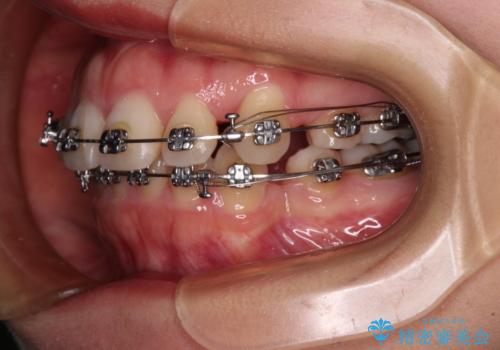

- メタルブラケット

- 2年4ヶ月

- 10-30回

口元を積極的に引っ込めるために、上下左右の第一小臼歯を4本抜歯することとし、ワイヤー装置による矯正治療を行うこととしました。

上下前歯がくちばしのように突出していましたが、抜歯矯正により口元が引っ込み、唇が閉じやすくなり、鼻の下の膨れた感じも解消されました。